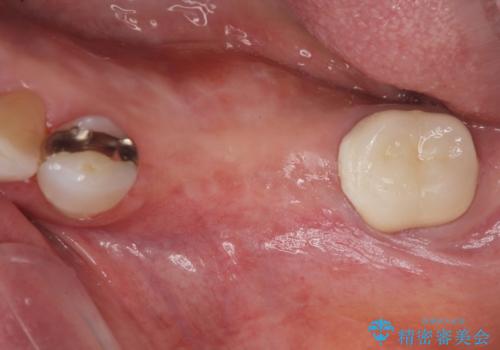

- 歯を喪失してしまい、咬合機能の回復を求めて来院されました。

入れ歯ではなく、よりしっかりと噛めるようになるインプラント治療を希望されましたが、将来的な安定を見込むにはインプラント周囲の骨量が少ない状況でした。

舌側にある大きな骨隆起を除去するとともに、除去した骨と人工骨を用いてインプラント周囲の骨を造成します。